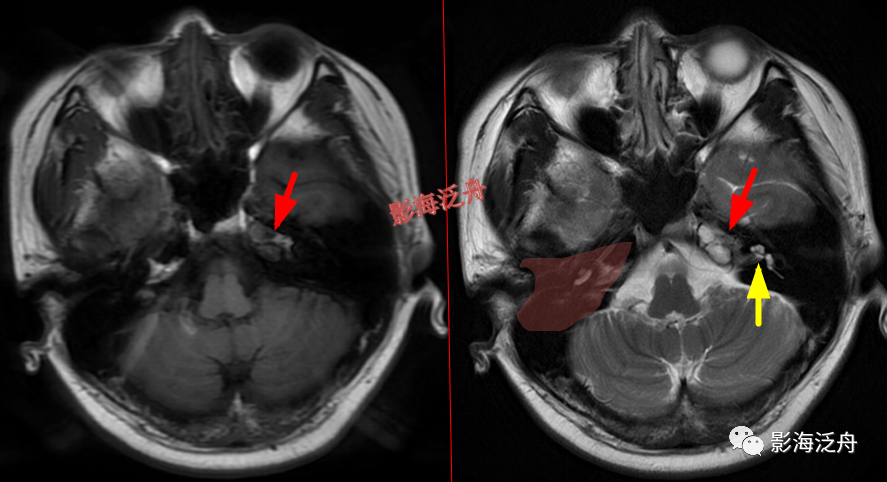

脑膜炎患者,桥前池内可见异常增多的血管影(红箭),正常人的桥前池因为脑脊液流动产生的伪影也可以看到池内絮状低信号(绿箭),但不如右侧患者的明显,这个观察起来比较困难,就如在腹部CT上观察患者是否存在肝脏肿大一样,需要一个经验积累的过程。黄箭指基底动脉,蓝箭指三叉神经。

颅骨病变

左侧岩尖部囊性病变(红箭头),患者未术,病理不明。MR对骨质结构显示不佳,因此很多读者会忽略掉颅内骨质病变的观察,很多颅内病变,如三叉神经鞘瘤、鼻咽癌等都会造成颞骨岩部(红色标注区)骨质破坏,因此,平时应对此处多加留意。黄箭头指听神经及内耳结构。

蝶骨骨纤维异常增殖症(红箭头),病灶内部可见特征性的囊变区(黄箭)。蝶骨的病变在MR上识别起来更为困难,因为蝶骨位于颅底部,此处骨骼、肌肉、脂肪等多种组织成分混杂,导致正常情况下也看起来非常乱。不要着急,慢慢学。